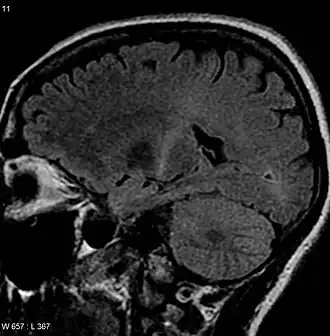

- Daarnaast kan een ALS-patiënt frontotemporale dementie ontwikkelen. Frontotemporale dementie (FTD) is een drastische verandering van gedrag en taalvaardigheid door het verlies van zenuwcellen in frontale en temporale hersengebieden. Bij ongeveer 15% van de patiënten met ALS treedt FTD op. FTD grijpt in op aspecten die behoren tot de kern van het mens-zijn: taal, persoonlijkheid en de manier van omgaan met anderen.